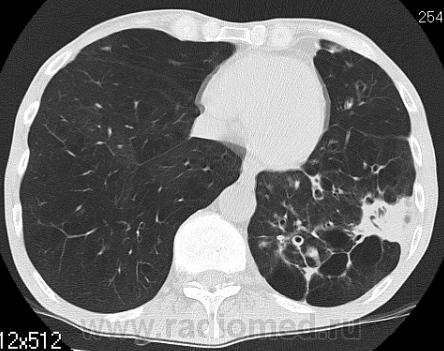

На фоне консолидации полость без содержимого. Может быть всё что угодно, что сопровождается деструкцией. Нужны ещё томограммы в лёгочном окне.

Изображения выставлены все. Ваше мнение уважаемые коллеги?

Туберкулёз.

Туберкулёз?

Это КТ 2-летней давности и попало оно мне в руки, после недавнего прохождения контроля пациентом, когда мы стали перед вопросом о специфическом / не специфическом процессе.

Тогда, пациента 2 месяца лечили от пневмонии, лечили интенсивности, стационарно, в серьёзном учреждении.

Предположу аспергиллез